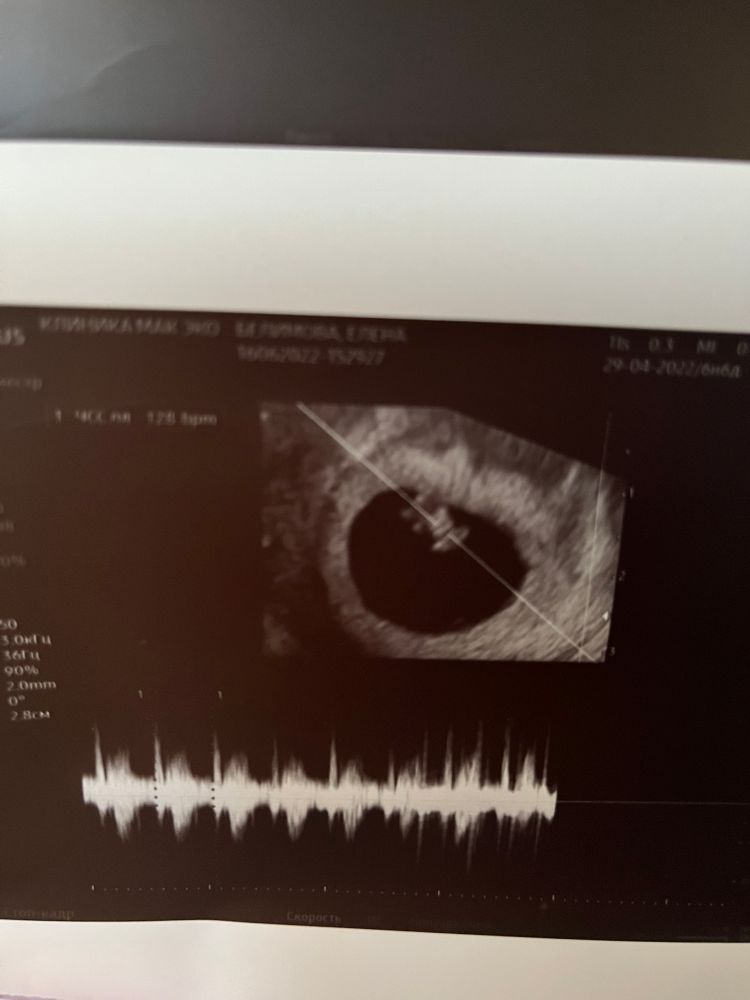

Результаты узи на фото.

По срокам - по размеру ПЯ идём день в день по акушерскому сроку, по КТР отставание на 2 дня. Но это ерунда, нагоним😉